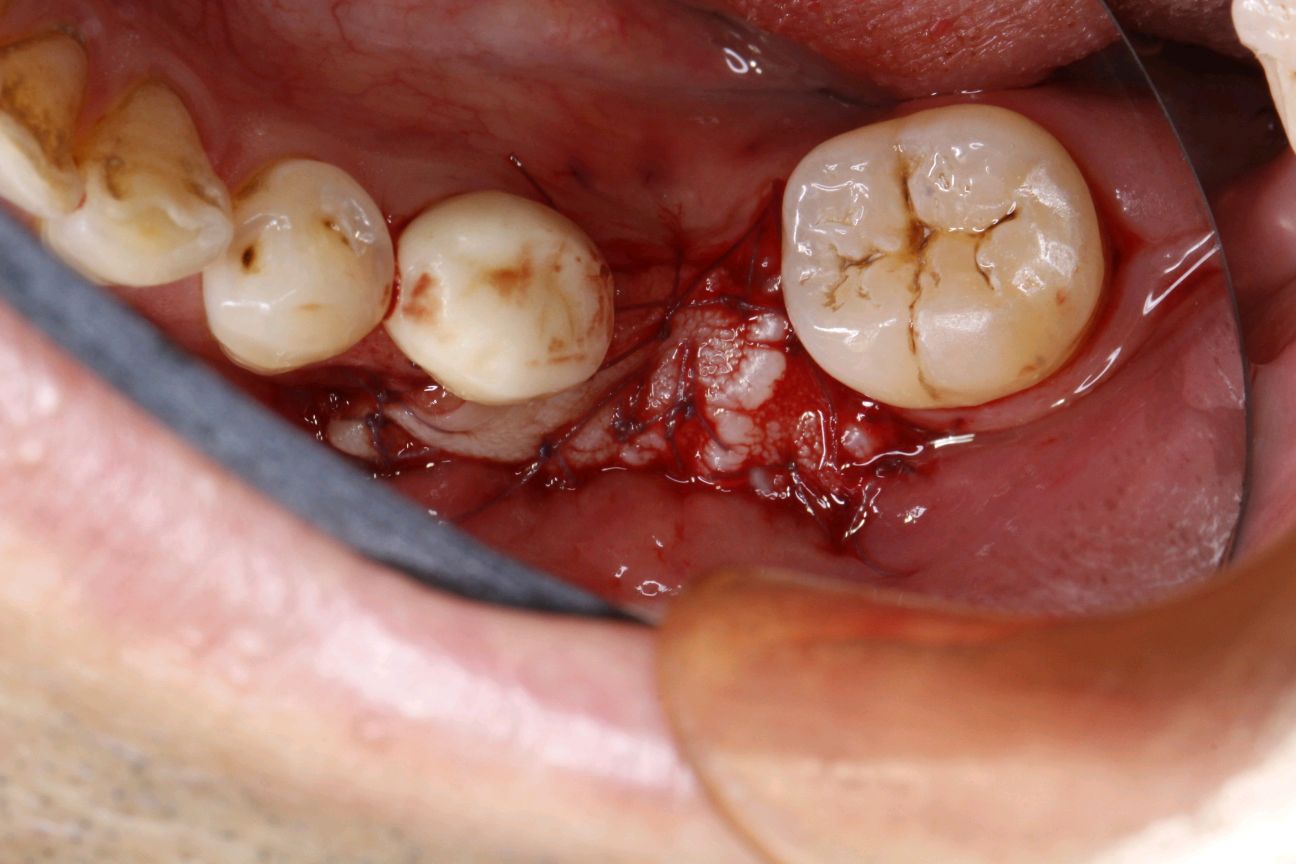

供区制备:第一前磨牙与第一磨牙近中根,距牙龈边缘2mm处制作非全厚切口,获得一个上皮组织瓣。

缝合完成移植瓣与受区骨膜的固定。确保无松动。